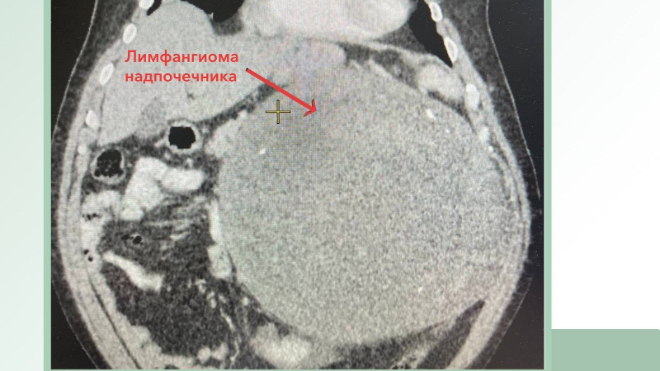

Как рассказали во вторник, 8 августа, в пресс-службе клинической больницы, опухоль мужчины оказалось редкой лимфангиомой надпочечника. Её вес достигал 10 килограммов. Кроме того, в левой почке у пациента обнаружили множественные мелкие злокачественные образования.

Несмотря на сложность, хирурги смогли удались почку и лимфангиому, которая занимала всю левую половину брюшной полости и отдавливала крупные сосуды.